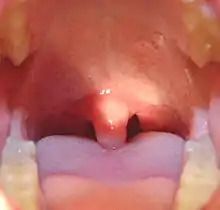

Uvula

The uvula (PL: uvulas or uvulae), also known as the palatine uvula, is a conic projection from the back edge of the middle of the soft palate, composed of connective tissue containing a number of racemose glands, and some muscular fibers.[1][2] It also contains many serous glands, which produce thin saliva.[3] It is only found in humans.[4]